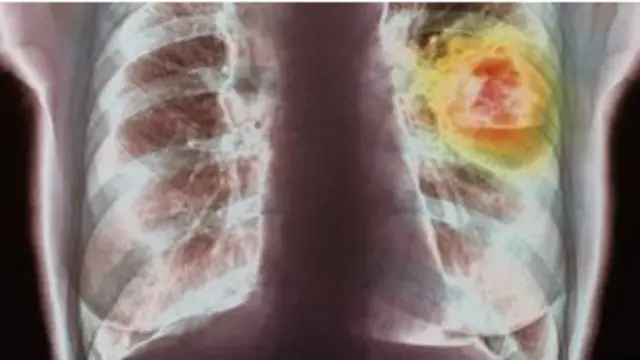

Cancer igeramiye isi

Ahavuye isanamu,

Abantu miliyoni 14 baratorwa cancer buri mwaka ariko bashobora kuba bageze ku miliyoni 19 mu mwaka wa 2025,22 mu 2030 na 24 mu 2035.